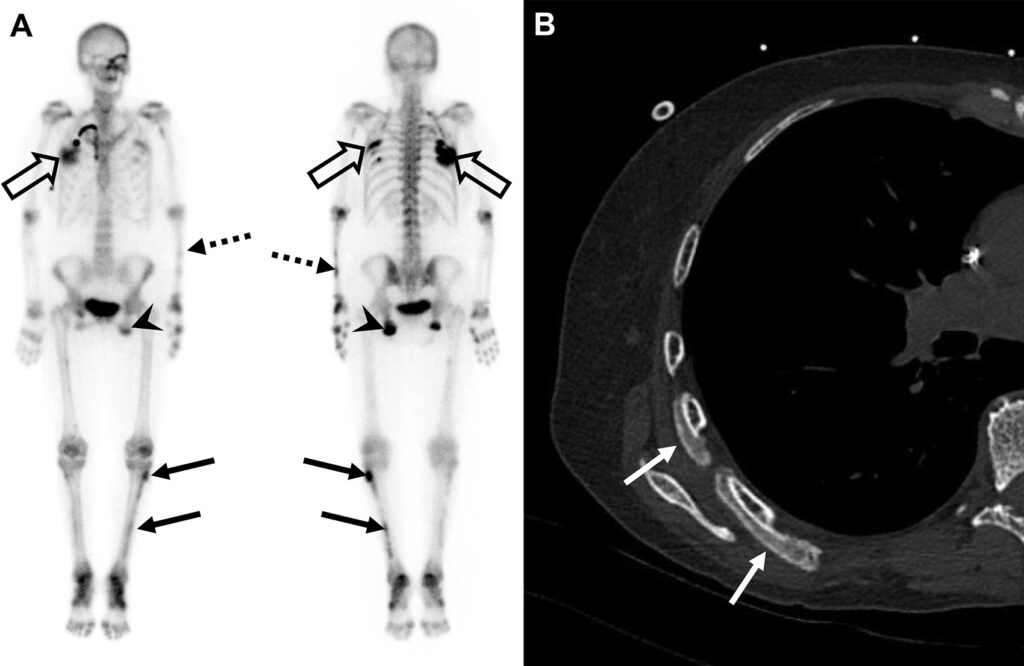

Periostite indotta da voriconazolo in una donna di 62 anni con linfoma a cellule T che ha sviluppato una coccidioidomicosi polmonare.

L’esame scintigrafico evidenzia un’ipercaptazione diffusa ma asimmetrica a carico del periostio, con un pattern misto (lineare sulle ossa lunghe, a chiazze sulle coste e globulare a livello ischiatico).

La TC del torace conferma la base fisiopatologica del reperto funzionale, documentando un’intensa (“florida”) apposizione di nuovo osso periostale a carico degli archi costali destri.

La periostite indotta da voriconazolo è una complicanza scheletrica ben documentata e dolorosa che può insorgere in pazienti sottoposti a terapie prolungate con questo farmaco antifungino. Poiché il voriconazolo contiene fluoro, l’accumulo cronico può determinare una fluorosi iatrogena, stimolando un’abnorme reazione osteoblastica periostale. La scintigrafia ossea è lo strumento d’elezione per mappare l’estensione dell’interessamento scheletrico sistemico.